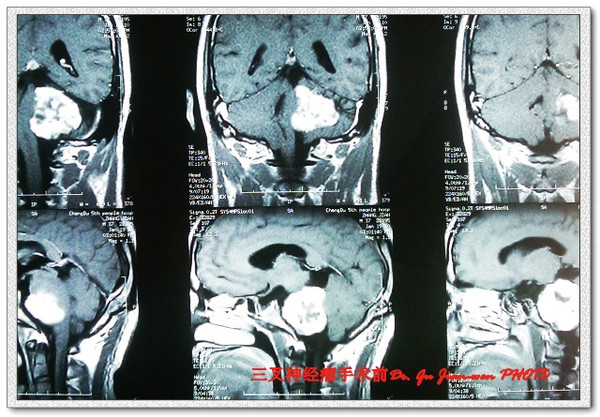

该例患者术前影像